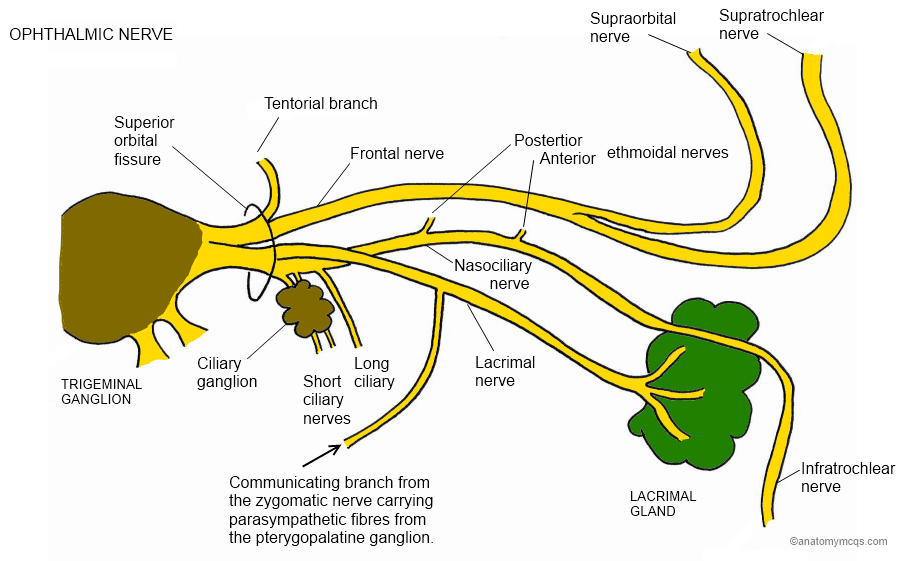

Nervo oftálmico V 1

Sai do gânglio do trigémio e dirige-se superiormente para atravessar a fissura orbital superior.

Dá as seguintes ramas:

Nervo Frontal

Nervo lacrimal

Nervo nasociliar

Este nervos, todos sensitivos são responsáveis pela informação do tipo tacto, dor, temperatura e informação proprioceptiva da conjuntiva, córnea, olho, órbita, testa, etmoide e seios frontais.

O nervo lacrimal leva informação sensitiva da glândula lacrimal, mas não é responsável pela sua secreção (provém do parassimpático do VII).

O nervo nasociliar inerva toda a mucosa da cavidade nasal e dos seios aéreos etmoidais.

O principal local onde este nervo pode ser perturbado é a nivel da fissura orbital superior, ou seja entre a ala maior e menor do esfenoide.

Quando existe uma perturbação a este nivel além das dores no território cutáneo de V1, podemos ter alterações lacrimais, de iridodilatação (pela relação com o gânglio ciliar), e dores no olho (bastante comum em consulta).

Por isso, sempre que suspeitarmos de uma lesão a este nivel, devemos rever os ossos em relação com o esfenoide nesta zona, nomeadamente o frontal, etmoide, maxilar superior, unguis e temporal, sem nos esquecermos do anel de zinn.